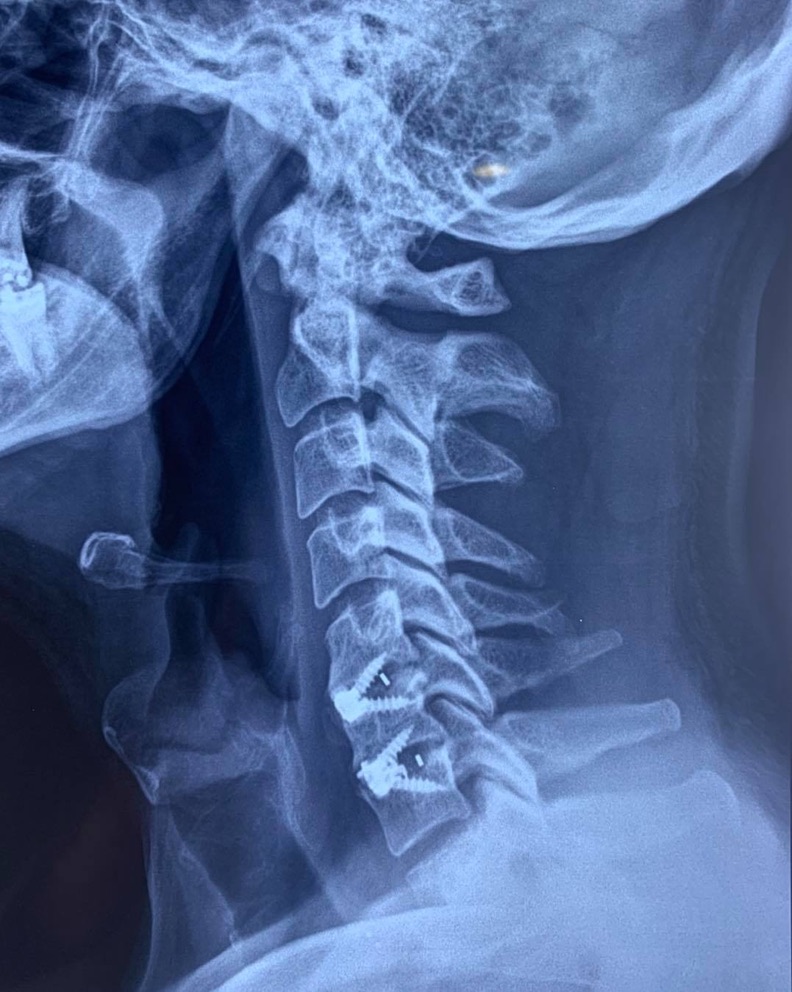

SURGERIES